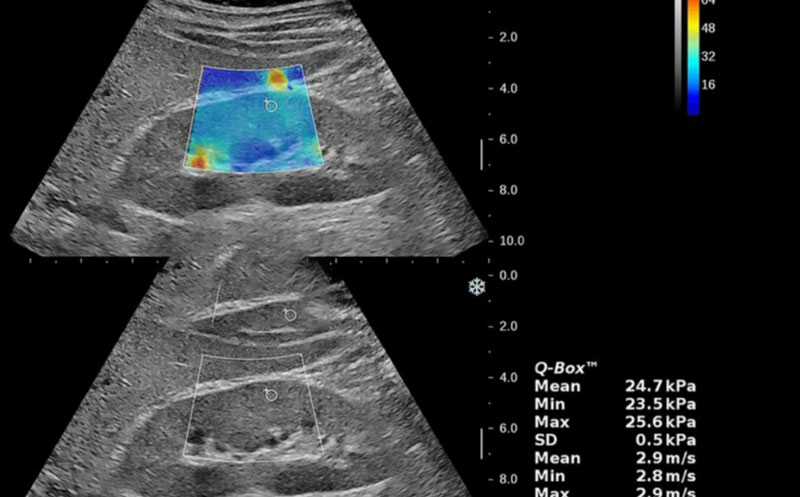

در جواب فیبرو اسکن کبد معمولاً دو پارامتر اصلی گزارش میشود:

- LSM (Liver Stiffness Measurement): اندازهگیری سفتی کبد به کمک کیلو پاسکال (kPa)

تفسیر مقدار LSM (درجه فیبروز)

| نمره فیبرو اسکن | محدوده kPa | شدت فیبروز | تفسیر ساده |

| F0 | < 5.5 | بدون فیبروز | کبد سالم |

| F1 | 5.5 – 7.0 | خفیف | آغاز تغییرات بافتی |

| F2 | 7.1 – 9.5 | متوسط | فیبروز مشهود |

| F3 | 9.6 – 12.5 | شدید | خطر نزدیک به سیروز |

| F4 | >12.5 | سیروز | آسیب شدید کبدی |